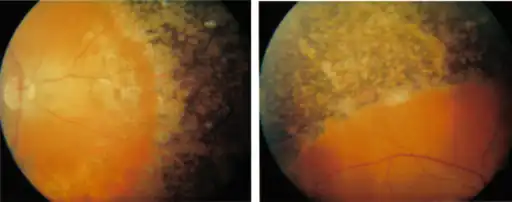

Extensive perivascular pigmentation seen in both fundi

Extensive perivascular pigmentation seen in both fundi -